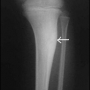

Bu tip de yüksek dereceli (high grade) bir osteosarkomdur. Yaş, cins ve lokalizasyon açısından fark yoktur. Kemiğin mekanik direnci çok zayıfladığı için hastalar sıklıkla (özellikle ilerlemiş dönemlerde) kendiliğinden oluşan kırıklarla (patolojik kırık) hekime başvururlar. Hastanın cerrahi tedavisi yapılana kadar (ameliyat öncesi kemoterapi aldığı dönemde) istenmeyen kırıkların oluşmasını engellenmek için uzuv mutlaka yükten korunmalıdır (alçı, değnek, vb.)

Radyolojik görüntü, anevrizmal kemik kisti ve bazen de soliter kemik kisti gibi selim kemik lezyonlarıyla karışabilir. Deneyimli olmayan bir göz, telanjiektatik bir osteosarkomu bu tür selim lezyonlarla karıştırıp biopsiye gerek duymadan tedaviye giderse bu dramatik sonuçlara yol açabilir. Tedavi protokolü klasik osteosarkom gibidir.